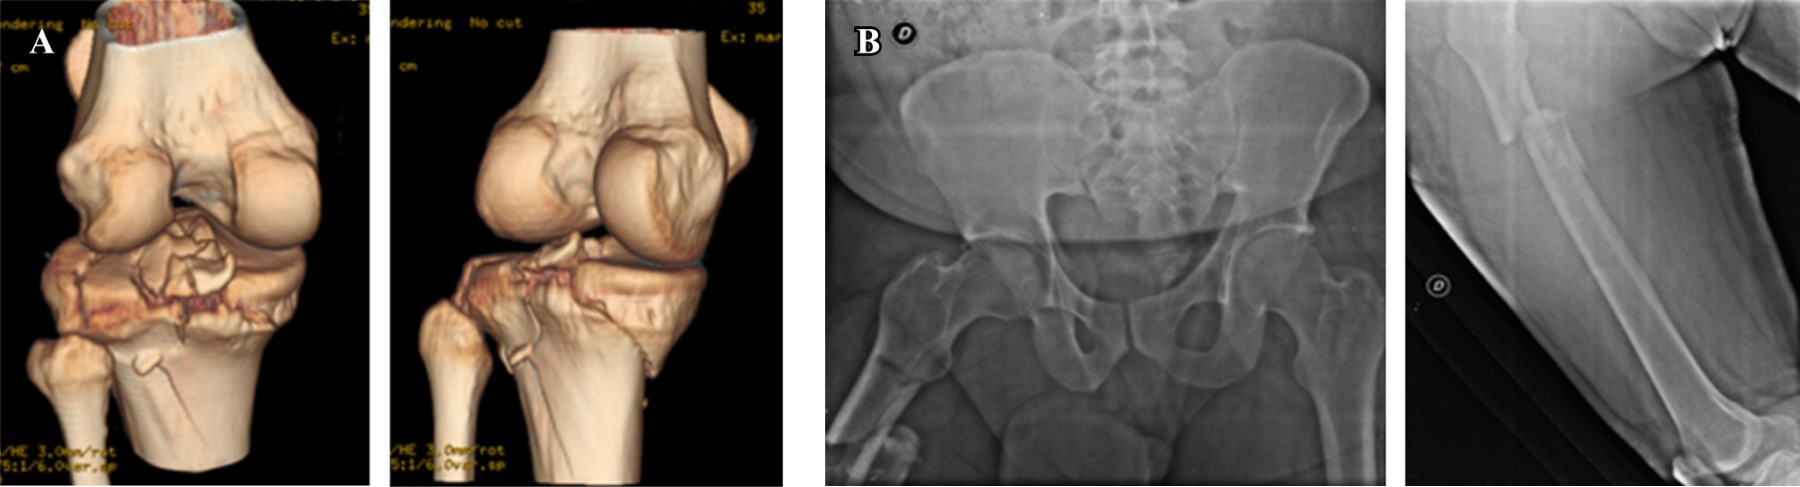

Paciente masculino de 41 años de edad quien ingresó en 2016 al servicio de urgencia con politraumatismo producto de accidente de tránsito; con trauma en miembros inferiores, en los rayos X se observa fractura de platillos tibiales izquierdos y fractura subtrocanteriana derecha (Figura 1), trauma toracoabdominal y trauma craneoencefálico leve.

Se le practica osteosíntesis de fémur con clavo cefalomedular largo a foco cerrado corrigiendo la fractura subtrocanteriana y se le aplica tutor externo transarticular de rodilla como medida de control de daño local provisional; 15 días después se realiza osteosíntesis definitiva de su fractura de platillos tibiales. Evolución adecuada y satisfactoria de platillos tibiales (Figura 2).

Figura 1

Figura 2